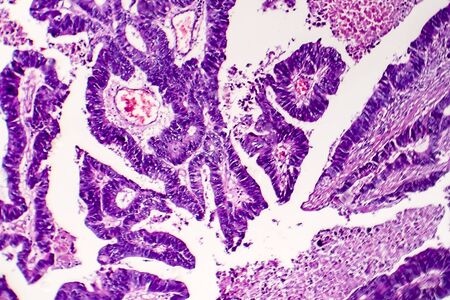

Ovarian cancer, light micrograph, photo under microscope. Photograph shows a fragment of a cancerous tumor in the female ovary. Selective focus